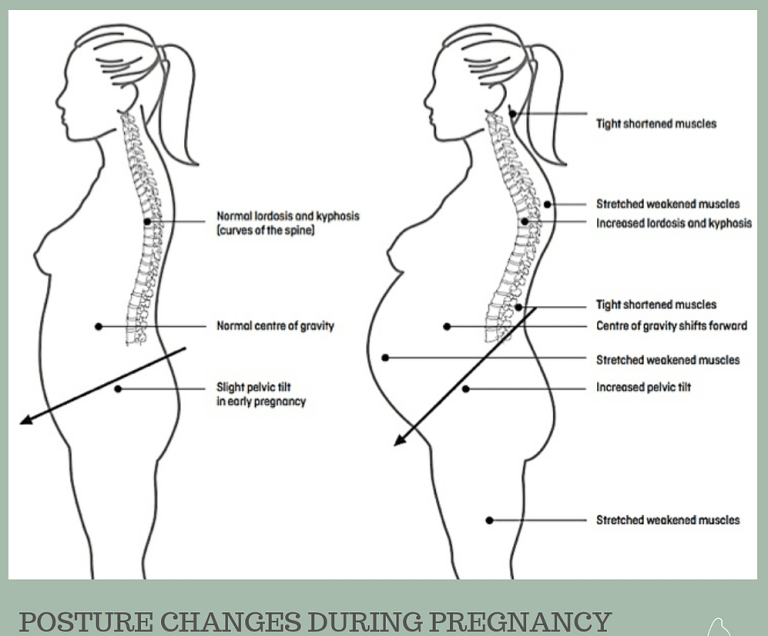

Low Back Pain In Pregnancy Loving Parents

Low Back Pain In Pregnancy Loving Parents

When Do Hips Start Hurting In Pregnancy Health Blog